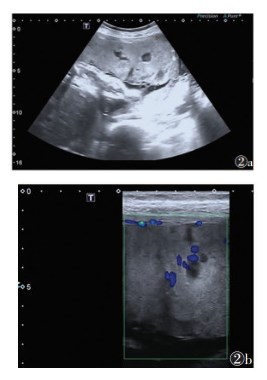

36例胎盘植入中,20例胎盘附着于子宫前壁合并前置胎盘(图 1)。低频超声漏诊3例中,2例胎盘位于子宫后壁并无前置,超声探查胎盘效果不佳,经验不足而漏诊;1例前壁胎盘,无前置,超声图像不典型而漏诊,此孕妇有人工流产史,联合高频超声检查后发现子宫后间隙部分消失子宫肌层变薄,诊断为部分植入。低频超声诊断假阳性3例均为前置胎盘,其中1例联合高频超声检查后确诊为前置胎盘无植入(图 2)。

| 图 2 38岁,孕36周,前置胎盘 图 2a 低频超声可见胎盘增厚,内部多发大小不等“胎盘陷窝”,胎盘陷窝部分呈云雾状;胎盘后间隙无法探及,胎盘后方子宫壁肌层低回声带似变薄或消失,可疑胎盘植入 图 2b 高频超声示胎盘后间隙存在、胎盘与子宫肌层之间界限清晰、局部肌层无明显变薄,CDFI示胎盘内部及胎盘后方无紊乱血流 |